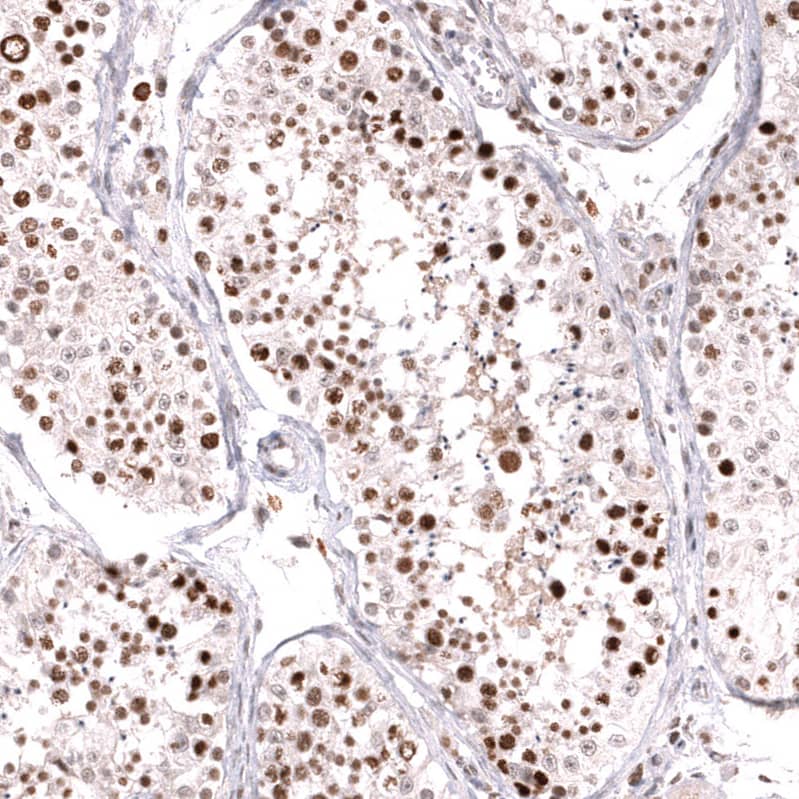

Orthogonal Strategies: Analysis in human testis and skeletal muscle tissues using NBP3-43857 antibody. Corresponding MSH6 RNA-seq data are presented for the same tissues.